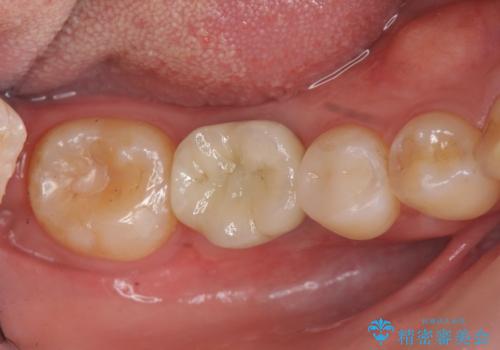

- 44万円(ストローマンインプラント・チタンカスタムアバットメント・仮歯・ジルコニアクラウン)費用は治療当時の料金となります

虫歯の放置により吸収してしまった骨も造成を行うことでインプラント周囲環境をしっかりと整えています。